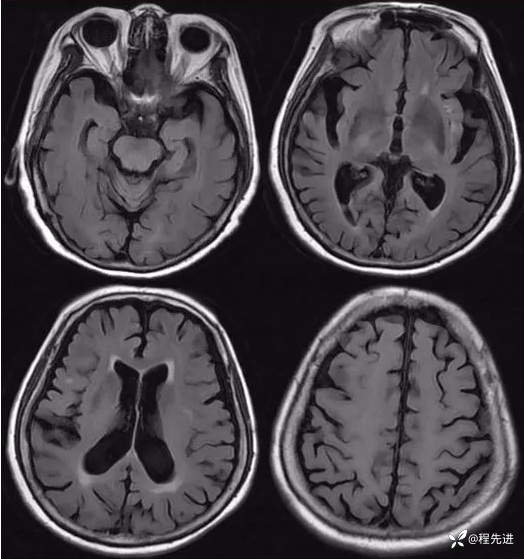

FLAIR: